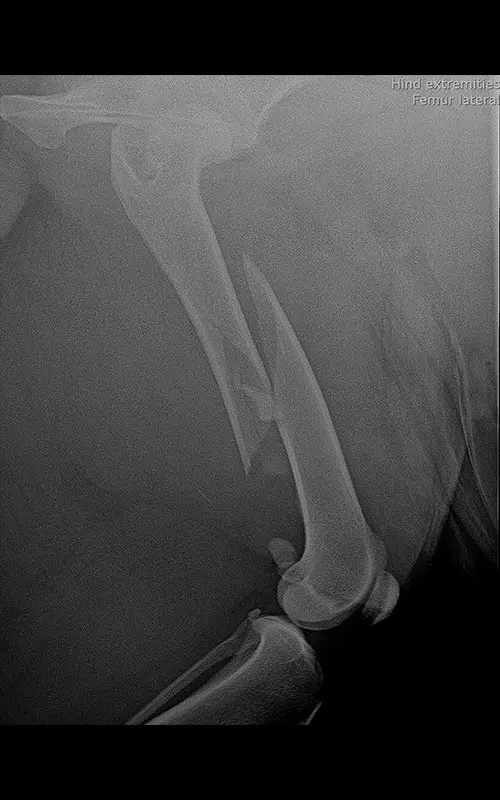

In our case, a 10-year-old labrador is involved in a car accident and his left femur and right tibia are severely injured. The dog had difficulty moving anyway due to severe hip arthrosis. During one surgical narcosis, K-pin - polyaxial locking plating was applied to both bones, the larger fragments were also fixed with 1-1 lag screws.